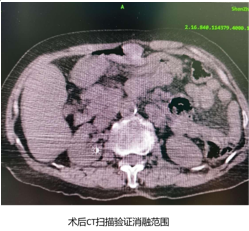

然后介入科沈新颖副主任医师在直视下将微波针经腹壁插入肝癌中,进行微波消融治疗,术中随时使用CT扫描验证入针角度、深度,腹腔镜直视下实时监控消融过程。共消融肿瘤4个不同位点,术后再次扫描CT验证消融范围,确保消融范围完全覆盖病灶。手术过程顺利,皮肤仅有2个不超过1cm的穿刺口。患者术后无任何不适症状,顺利康复出院。